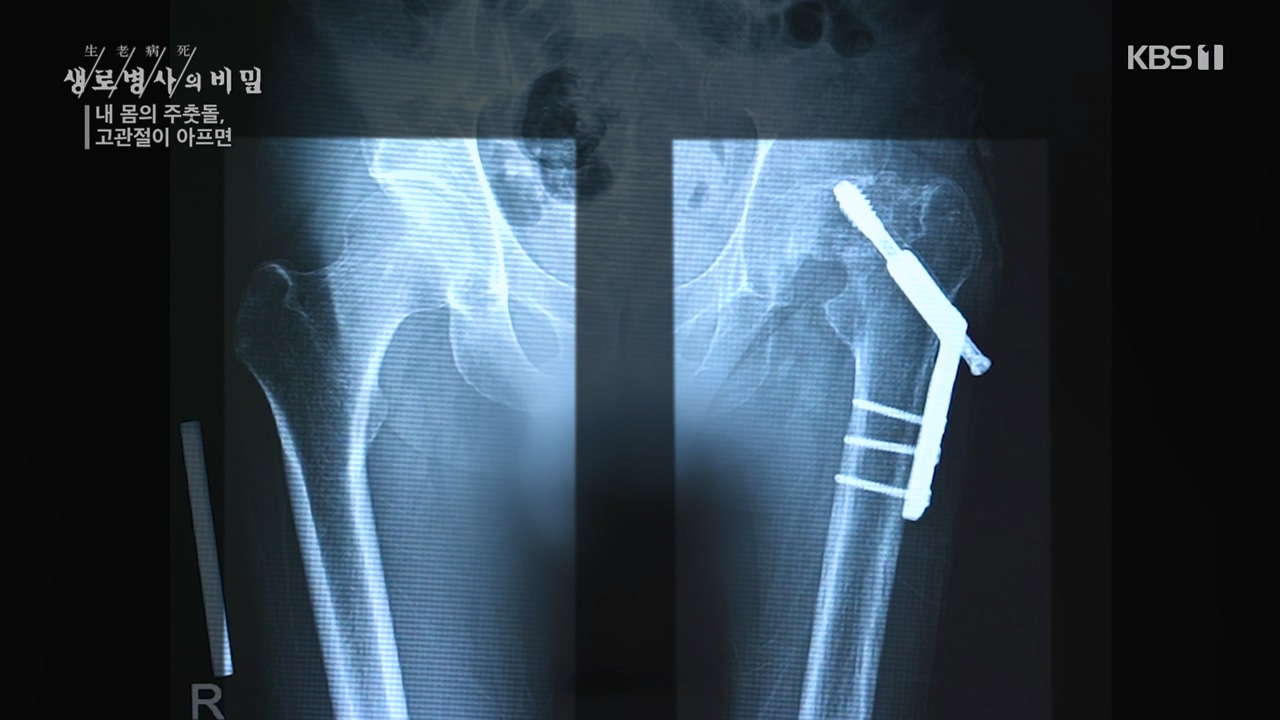

[박은철 기자] 앉고 서고 걷고 달리는 등 우리가 움직이는 순간마다 쉼 없이 일하는 관절이 있다. 엉덩이 관절이라고도 불리는 '고관절'은 상체와...